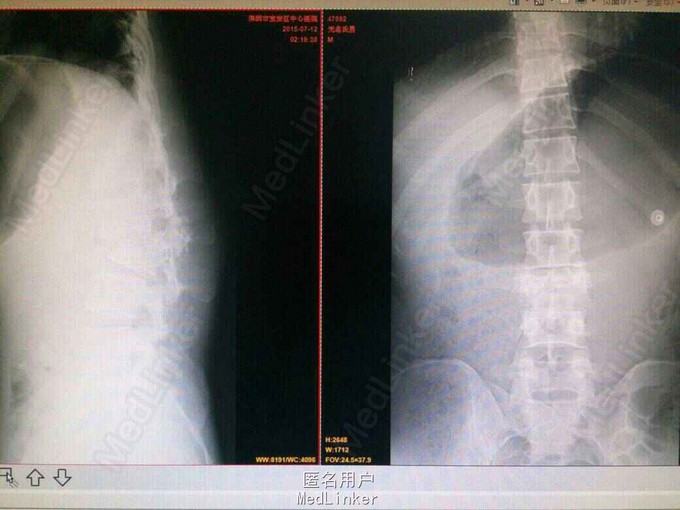

患者男性,20岁,高处坠落后腰痛,活动受限2小时入院,双下肢麻木无力,二便障碍。

查:腰部后凸畸形,压痛,叩痛,腰3平面以下痛觉减退,肌力:胫前肌:左I级,右IIl级,提睾反射消失。CT:腰3椎体爆裂性骨折,腰2椎体前滑脱。椎管严重占位。